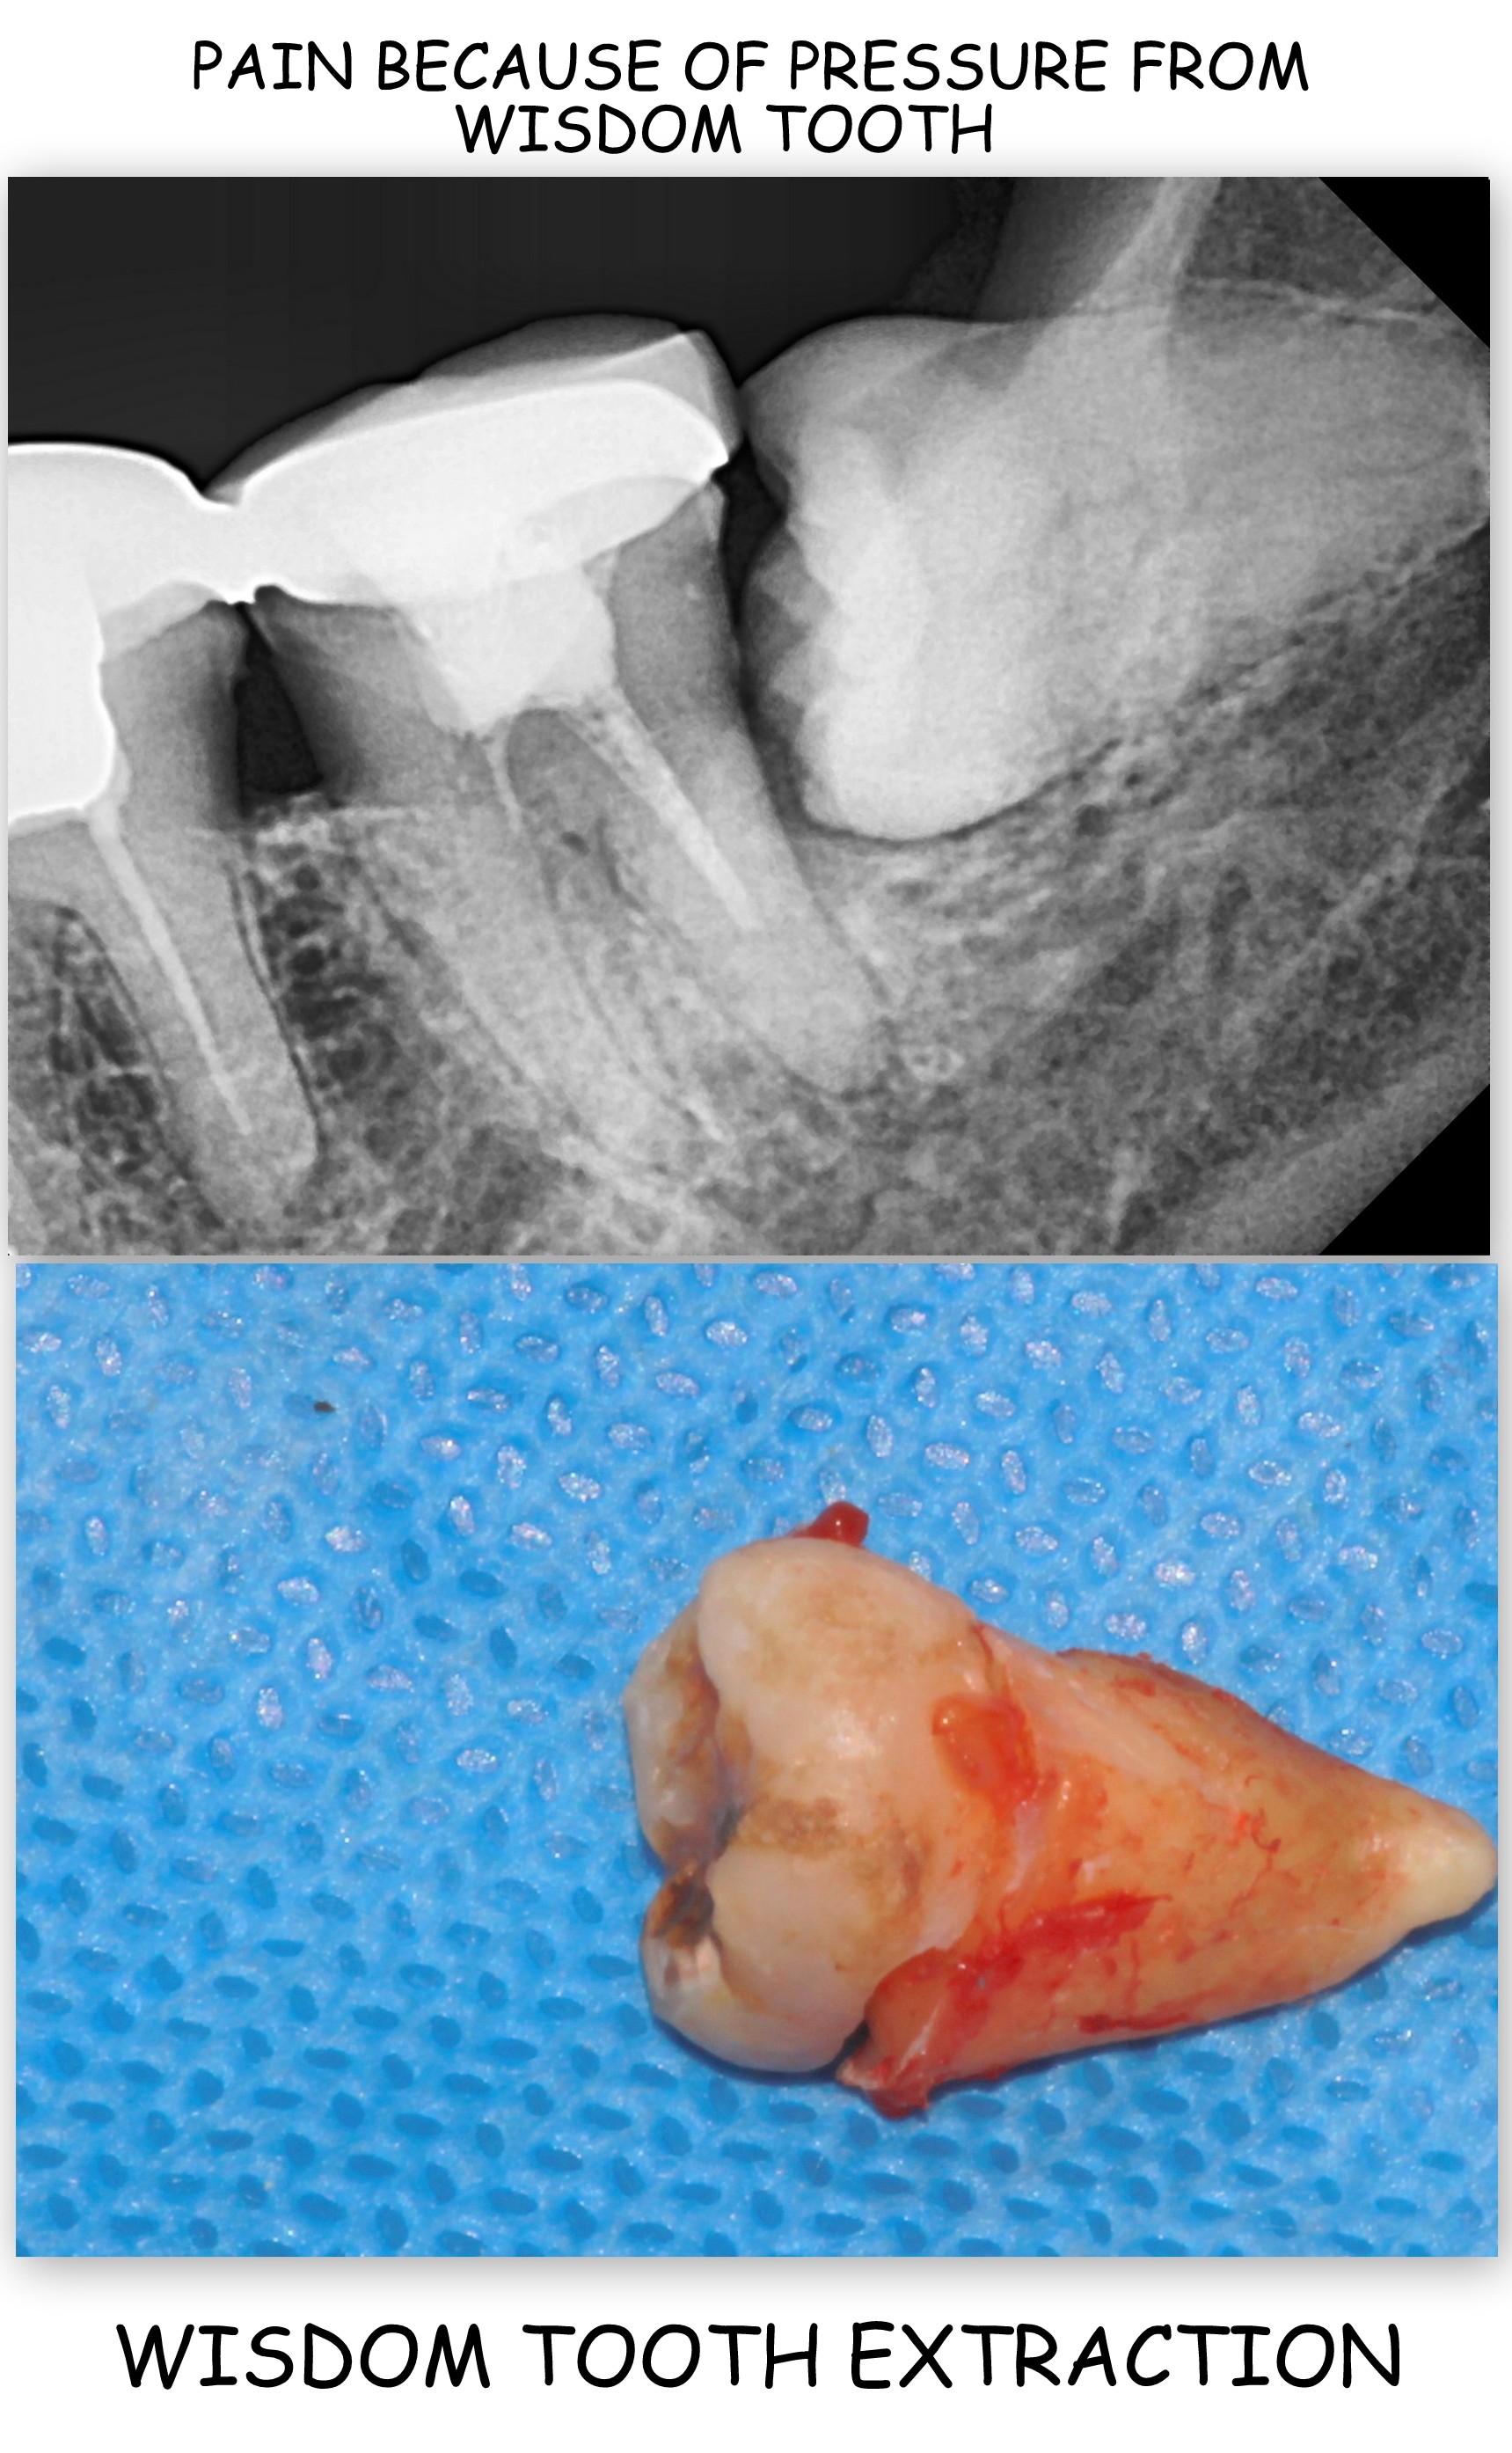

A wisdom tooth is the last molar tooth in the mouth that appears at a later age. Wisdom teeth are usually four in number two in the upper jaw and two in the lower jaw. Most often wisdom teeth do not have enough space to erupt straight in the mouth. Due to this they get decayed posing a threat to neighbouring teeth as well. Impacted wisdom teeth can be very painful and can cause constant nagging pain, ear/jaw ache, difficulty in opening the mouth /chewing etc. If left in the mouth for a long time they can develop infection which spreads to surrounding gums and bone.

Wisdom tooth extraction is recommended in cases of decayed, un-erupted or wrongly erupting last molar teeth. Symptoms of the above may be pain while opening their mouth or chewing food, severe or dull nagging tooth ache, ear/jaw pain, difficulty in eating due to swelling of gums around the tooth.

When carefully executed by skilled and experienced doctors it is a very safe and predictable procedure. Local anaesthesia is used and the teeth are carefully and delicately removed. In some cases surrounding bone may need to be trimmed to remove the tooth. The opening left after the extraction is sealed with stitches to avoid any bleeding and ensure healing.